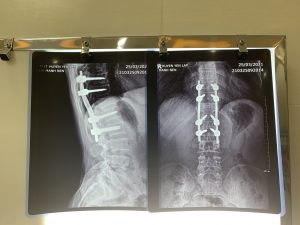

Cách đây 2 năm, do một tai nạn mà người bệnh H.M.N, 50 tuổi ở khu Minh Thượng, xã Phúc Khánh, huyện Yên Lập bị chấn thương cột sống. Để tránh các biến chứng do tổn thương tủy sống như rối loạn vận động, mất vận động, rối loạn cảm giác, thậm chí bị liệt,… người bệnh được phẫu thuật kết hợp xương thân đốt sống D10-L2 bằng nẹp vít. Ngày 25/3/2021, người bệnh nhập viện tại Trung tâm Y tế huyện Yên Lập để tháo phương tiện kết hợp xương

Ngày 26/3/2021, kíp phẫu thuật Trung tâm Y tế huyện Yên Lập cùng với sự hỗ trợ chuyên môn từ các chuyên gia khoa Ngoại thần kinh, Bệnh viện Đa khoa tỉnh Phú Thọ người bệnh được tiến hành phẫu thuật tháo phương tiện kết hợp xương cột sống. Đây là ca phẫu thuật tháo phương tiện kết hợp xương phức tạp, đòi hỏi kíp phẫu thuật có trình độ chuyên môn sâu về lĩnh vực ngoại thần kinh, ngoại chấn thương bởi trong quá trình phẫu thuật rất dễ làm thương tổn các cấu trúc của cột sống hoặc tủy sống, dây chằng, đĩa đệm,…